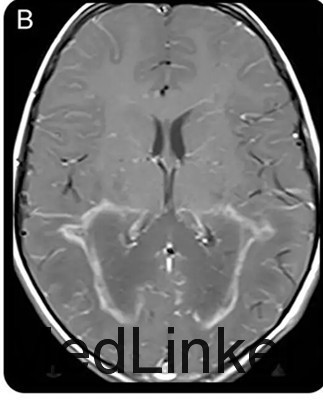

查体发现患儿皮肤色素沉着及低血压。神经系统查体提示理解困难,双眼视力下降、共轭凝视不良,辩距不良,步态不稳。脑脊液蛋白升高。头颅MRI如下图。清晨皮质醇水平降低,促肾上腺皮质激素兴奋试验证实肾上腺功能不全功能。神经遗传学检测提示ABCD1基因突变

ALD是一种先天性代谢性疾病,也是最常见的溶酶体病之一。属于X-连锁遗传病。本病特征性的影像学改变是MRI可见双侧顶枕区白质对称性分布的蝴蝶样长T1长T2信号,早期即可以胼胝体压部受累,并将两侧病灶连为一体。(神经病学俱乐部)本病一般预后较差,在出现神经症状后1~3年死亡。